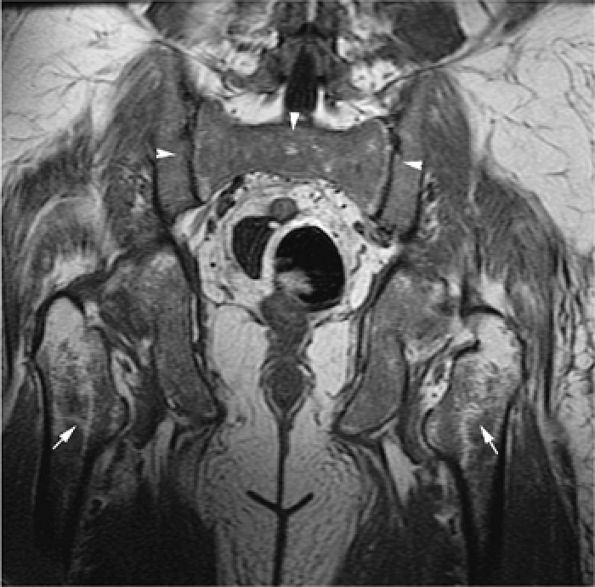

![]() |

FIGURE 13.22 ● The patchy (arrows) and diffuse (arrowheads) pattern of leukemic marrow infiltration in hairy cell leukemia demonstrates low signal intensity on a coronal T1-weighted image of the pelvis.